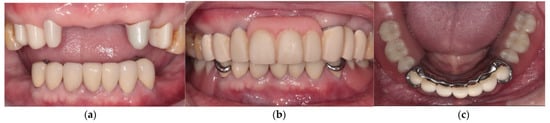

3. Results